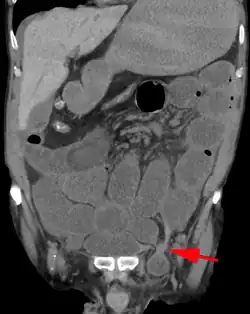

A frontal view of an incarcerated inguinal hernia (on the patient's left side) with dilated loops of bowel above.

An inguinal hernia which contains part of the bladder. Bladder cancer is also present.